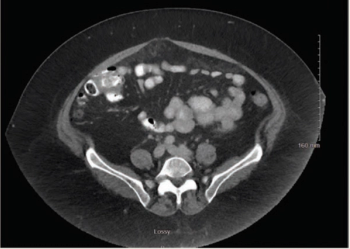

Mucinous Adenocarcinoma of the Appendix With Histologic Response to Neoadjuvant Chemotherapy: Review of Histologic and Clinical Spectrum of Epithelial Neoplastic Mucinous Lesions of the Appendix

ByMehmet Sitki Copur, MD,Allison M. Cushman-Vokoun, MD, PhD,James Padussis, MD,Whitney Wedel, MD,Caleb W. Schroeder, MD,Daniel J. Herold, MD,Nicholas Lintel, MD,Adam J. Horn, MD Mehmet Sitki Copur, MD, and colleagues examine the case of a 65-year-old patient with appendiceal mucinous neoplasms of the appendix who was treated with cytoreductive surgery and hyperthermic intraperitoneal chemotherapy.